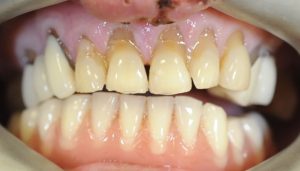

Pre-operative clinical views demonstrated the extent of the trauma and the compromised condition of the maxillary incisors . Radiographic assessment was carried out to evaluate the remaining bone support and to guide implant planning. The aim was to provide a fixed restoration with good functional and aesthetic predictability while minimising surgical intervention.

The final restoration re-established continuity of the anterior dentition and provided the patient with a fixed replacement following traumatic tooth loss.